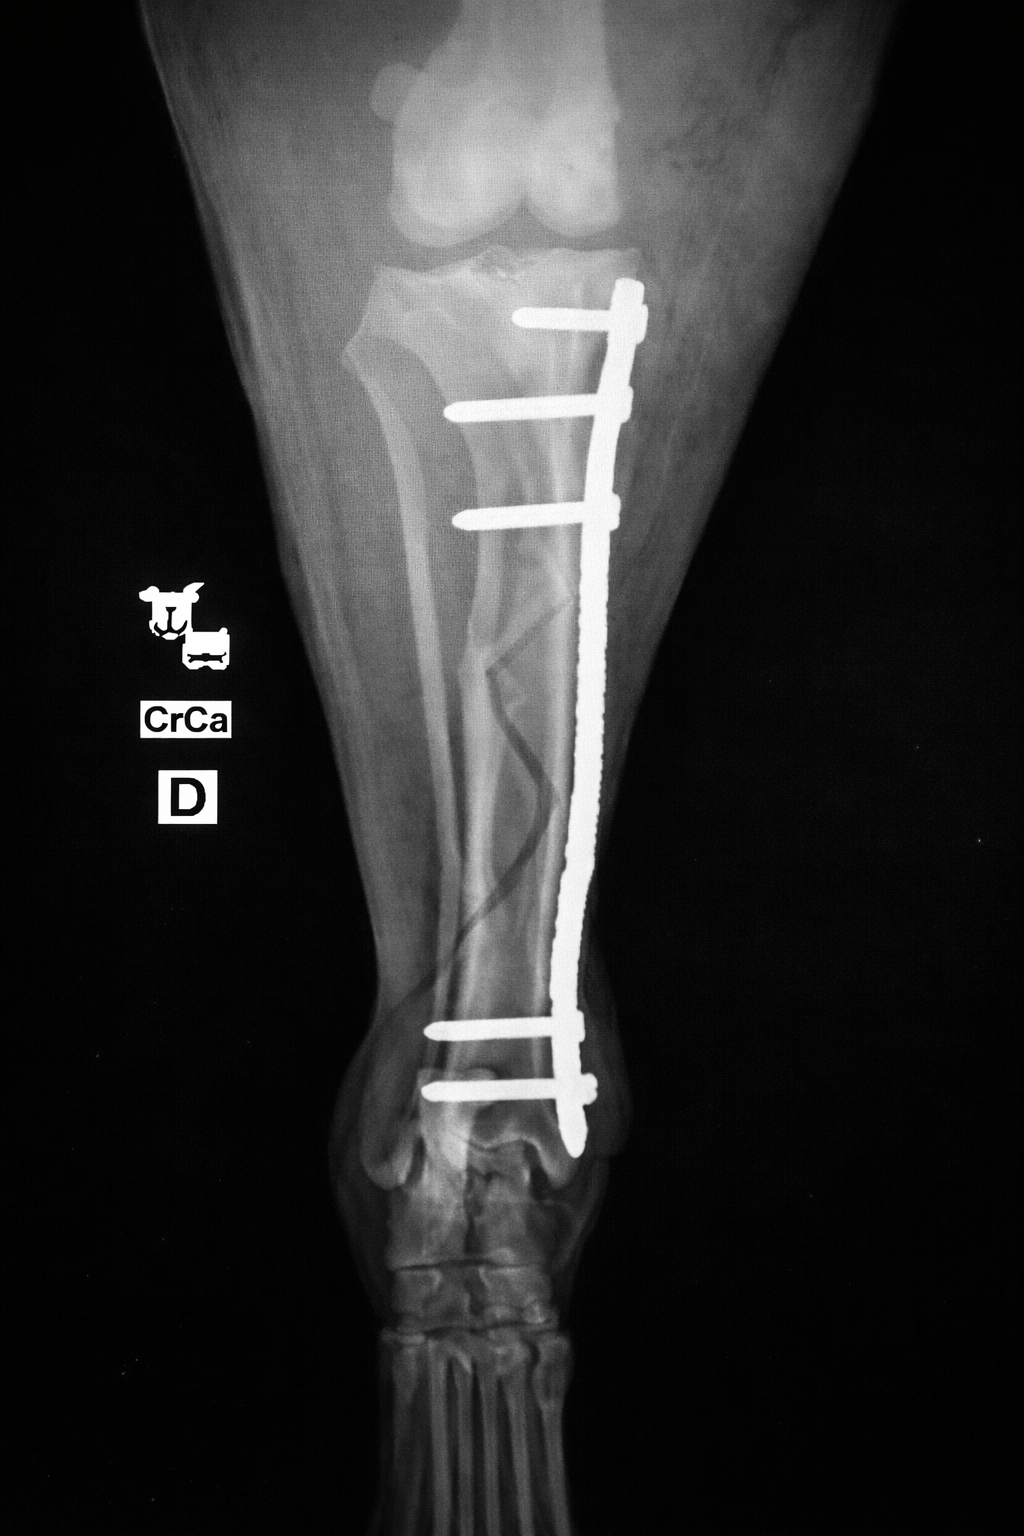

Kreuzbandriss – TPLO Hund

Die Ruptur des vorderen Kreuzbandes zählt zu den häufigsten orthopädischen Erkrankungen beim Hund.

Die TPLO (Tibial Plateau Leveling Osteotomy) ist ein bewährtes Verfahren zur funktionellen Stabilisierung des Kniegelenks und ermöglicht eine zuverlässige und langfristige Verbesserung der Gelenkfunktion.

Kreuzbandriss – TPLO Katze

Wie beim Hund kann auch die Katze mit der TPLO-Technik operiert werden. Die Methode stabilisiert das Knie, lindert Schmerzen und ermöglicht eine schnelle Genesung.